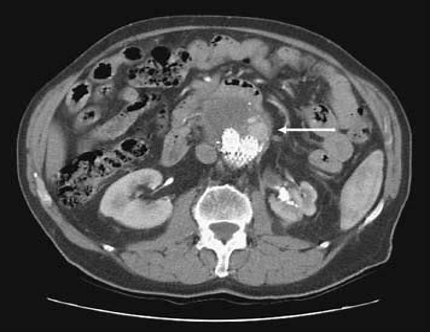

随访显现

long term follow-up whenever detected

Three-phase CTA at regular time, especially for patients with sac expansion.

Duplex US if no sac expansion